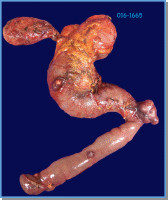

Mujer de 46 años con antecedente de múltiples lesiones en piel (foto 1 Y 2 ) desde la infancia. Inicia su padecimiento con pérdida de peso, distensión abdominal y vómito. La endoscopia mostró lesión ámpula de Váter y la TAC múltiples lesiones en duodeno (Foto 3). Se realizó Whipple. Foto 4.

Foto 4